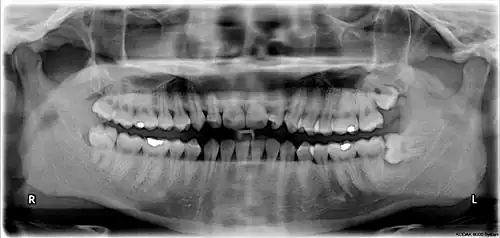

Wisdom teeth in the human mouth for permanent teeth. There are none in deciduous (children's) teeth. | |

The third molar, commonly called wisdom tooth, is the most posterior of the three molars in each quadrant of the human dentition. The age at which wisdom teeth come through (erupt) is variable,[1] but this generally occurs between late teens and early twenties.[2] Most adults have four wisdom teeth, one in each of the four quadrants, but it is possible to have none, fewer, or more, in which case the extras are called supernumerary teeth. Wisdom teeth may become stuck (impacted)[3] and not erupt fully, if there is not enough space for them to come through normally. Impacted wisdom teeth are still sometimes removed for orthodontic treatment, believing that they move the other teeth and cause crowding, though this is disputed.[4][5]